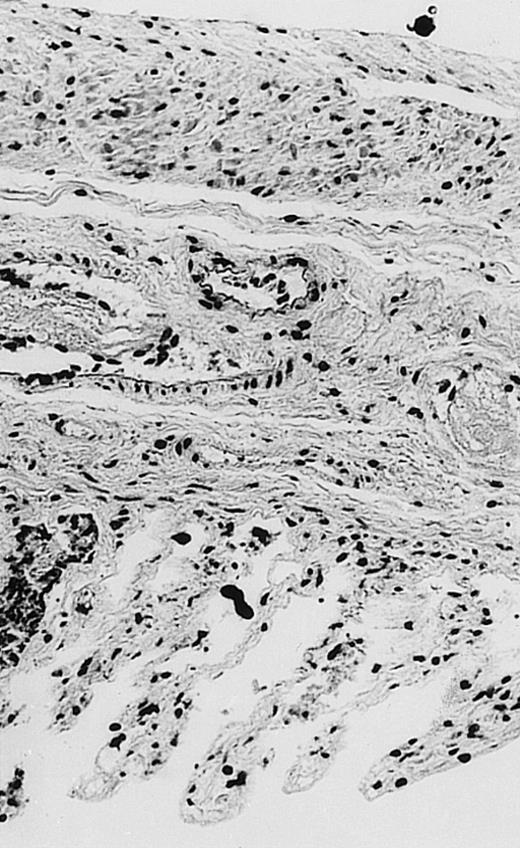

Pathologic findings in the small and large intestine were strikingly different depending on the treatment group. Figure 2A shows a representative pathologic sample from an animal assigned to the control group. Marked thinning of the bowel wall and extensive areas of epithelial cell sloughing was noted. Animals randomized to rhG-CSF treatment had minimal improvement in histologic findings with focal regions of preserved epithelium (Fig2B). Animals randomized to the rhIL-11 group showed substantial improvement with thickening of the epithelial layer and preservation of mucosal cell integrity (Fig 2C). Animals receiving both rhG-CSF and rhIL-11 had the most favorable histologic findings with normal mucosal thickness, minimal inflammatory changes, and preserved tissue architecture (Fig 2D). The composite analysis of the gastrointestinal pathology is provided in Table 1.

Histopathology of small intestinal mucosa cut in transection from an animal in each treatment group (study day 8). The upper panel (row 1) is a low power view (original magnification × 57); the lower panel (row 2) is a high power view (original magnification × 144). Note the diffuse thinning and necrosis of the mucosa with sloughing of intestinal epithelial cells in the control animal (A). There is progressive recovery of the thickness of the mucosa, reduction in inflammatory changes, and improved epithelial architecture with rhG-CSF (B), rhIL-11 (C), and combination therapy with rhG-CSF+IL-11 (D).

rhIL-11 has been shown to have marked effects on gastrointestinal epithelial surfaces. rhIL-11 blocks apoptosis of epithelial cells exposed to radiation and chemotherapy in mice.22 rhIL-11 is protective in a variety of mucositis models and in models of intestinal inflammation.4,23,24 rhIL-11 has been shown to prolong the G-0 phase of growth of intestinal epithelial cells. The precise mechanism of action is not known, but it has been observed that rhIL-11 decreased pRB (retinoblastoma protein) phosphorylation (an important signaling event in cell cycling) within intestinal epithelial cells.32 rhIL-11 has protective effects on gastrointestinal mucosa in transgenic rats, which possess HLA-B27 antigens.4These animals develop an inflammatory colitis that is similar in many respects to human inflammatory bowel disease. rhIL-11 treatment in these animals decreases intestinal inflammation and chronic diarrhea. Based on these preclinical findings, rhIL-11 is currently in clinical trials in both inflammatory bowel disease and chemotherapy-induced mucositis.33 The remarkable capacity of rhIL-11 to protect the gastrointestinal mucosal integrity after chemotherapy is apparent in the current series of experiments (Fig 2).

The beneficial effects of rhIL-11 in the neutropenic rat model may be mediated by its activity as a hematopoietic growth factor, an antiinflammatory cytokine, or its ability to maintain gastrointestinal epithelial integrity.25,33 The results of the current study would favor rhIL-11 protective effects on the intestinal epithelium as the principal mechanism protection in these animals. Maintenance of the gastrointestinal barrier function should diminish the frequency of gut translocation-derived bacterial infection after chemotherapy-induced myelosuppression and epithelial injury.25 The remarkable preservation of membrane integrity found on the gastrointestinal pathologic samples, the reduced circulating levels of endotoxin, and the reduced bacterial load in organ cultures support a dominant role for epithelial protective effects by rhIL-11 treatment in this animal model.